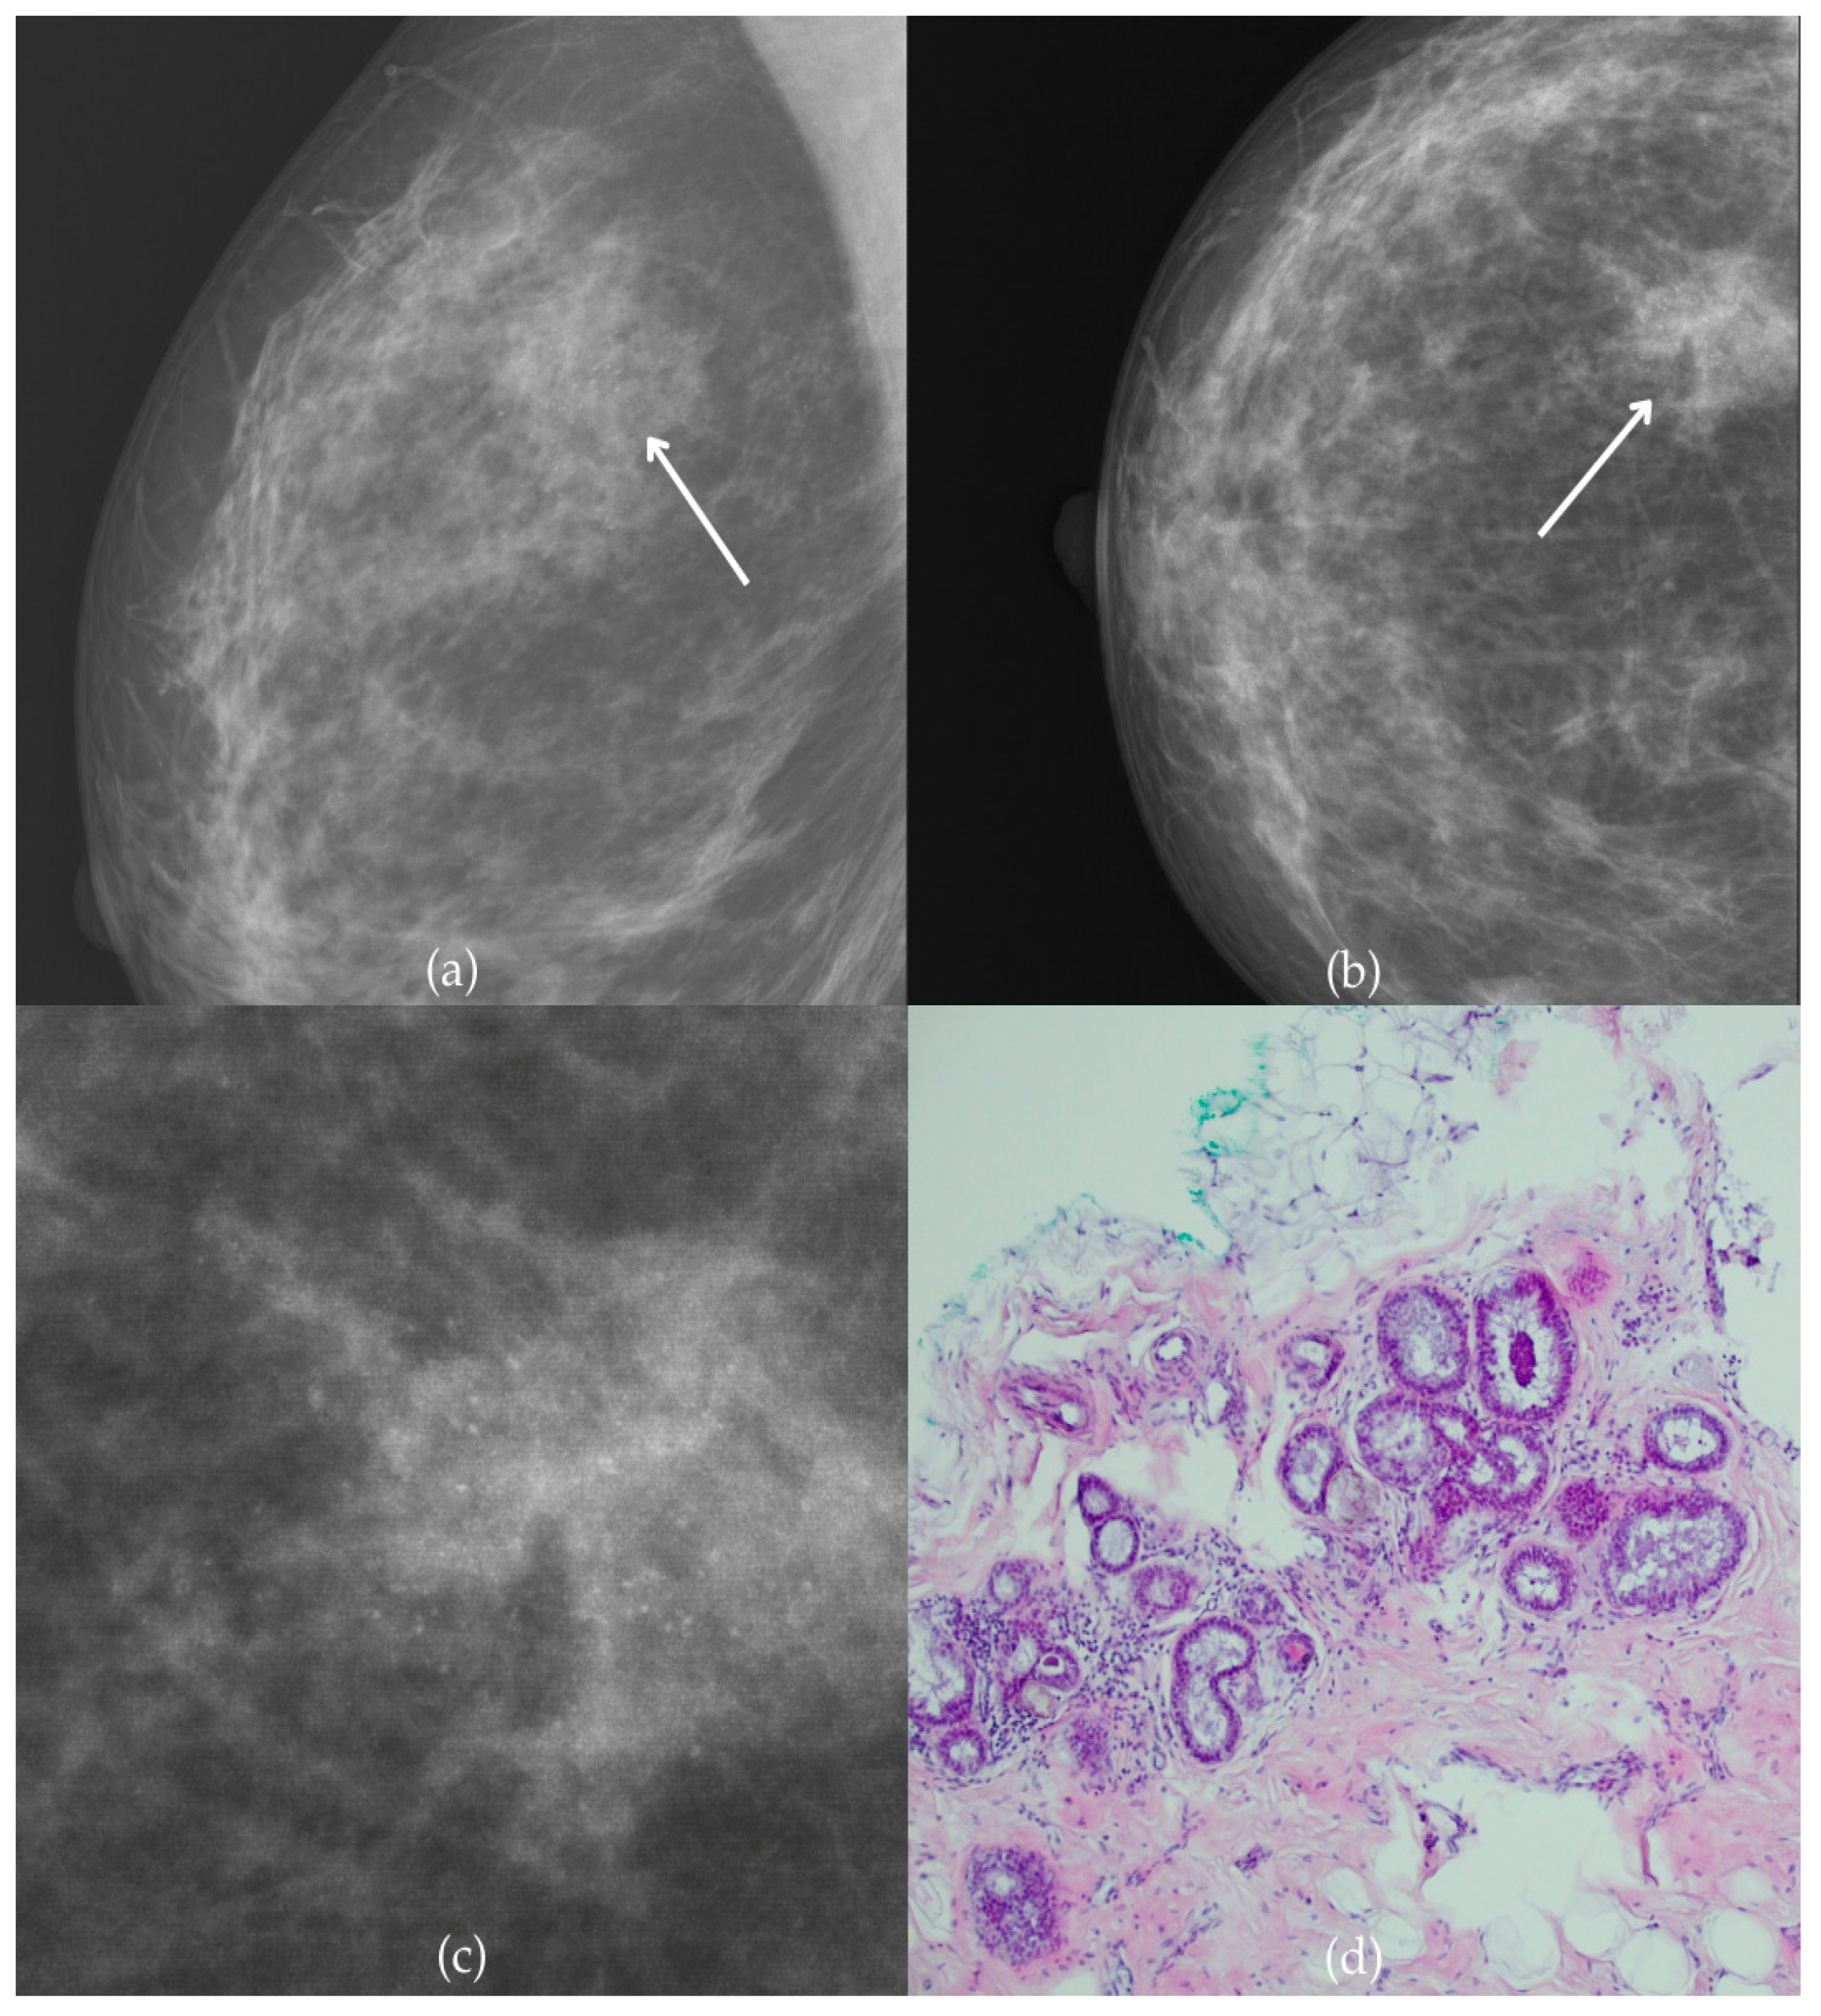

During a screening program, a 64-year-old patient presented with suspicious microcalcifications. The mammogram shown in Figure 3 of the patient’s right breast revealed a segmental distribution of coarse heterogeneous and fine pleomorphic calcifications in the upper outer quadrant, corresponding to a BI-RADS 4 finding. Tissue analysis obtained through VABB confirmed the presence of invasive carcinoma (category B5b). The patient underwent a mastectomy. Postoperative pathology showed only an in situ component, with no evidence of an invasive component, indicating that the invasive component was removed during the biopsy. One year after diagnosis, the follow-up US was reported as BI-RADS 2 classification, indicating benign imaging features.

Figure 3.

Invasive breast cancer. (a) Mediolateral oblique (MLO) mammography view; (b) craniocaudal (CC) mammography view of the right breast showing coarse heterogeneous and fine pleomorphic calcifications (marked with arrows) in the upper outer quadrant, with segmental distribution. (c) Magnified mammographic image of coarse heterogeneous and fine pleomorphic calcifications with segmental distribution. (d) The histopathological image of the biopsy sample shows the characteristic features of invasive cancer (marked with arrow) and ductal carcinoma in situ (DCIS) (marked with arrowhead) (HE staining; 40× magnification).